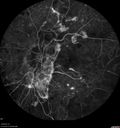

71 year old female - About 1 year ago the patient had injections in each eye and also started with laser. Hurricane Irma hit and she had her appointments cancelled and she did not go back. She had cataract surgery previously but no other treatment. About a month ago she noticed that her vision was declining in the left eye and then a few weeks ago it got a lot worse. The right eye is pretty good and she can see with her reading glasses. She is planning to get bifocals in the future. She did not want to get new glasses until we figured out the left eye. VA OD: sc20/25-2 VA OS: sc1’/200 IOP: TP: OD:15 OS:15 The left eye has no macular edema or macular detachment and an APD. The vision loss is likely from a CRAO or from optic atrophy. So a PPV was not done.

Severe PDR with preretinal fibrosis435 views71 year old female untreated for a year following injections because of hurricane Irma. VA 20/30 OD and 5/200 OS. Sudden vision loss 1 month ago left eye was likely an ischemic event. Right eye is being treated with injections and PRP laser.00000